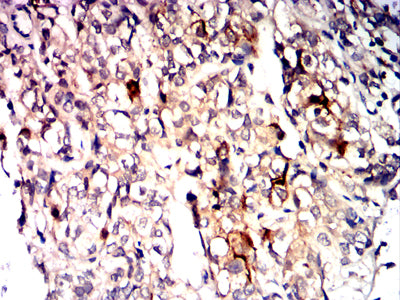

Immunohistochemical analysis of paraffin-embedded human bladder cancer tissues using CD10 mouse mAb with DAB staining.

-

Immunohistochemical analysis of paraffin-embedded human brain tissues using CD10 mouse mAb with DAB staining.